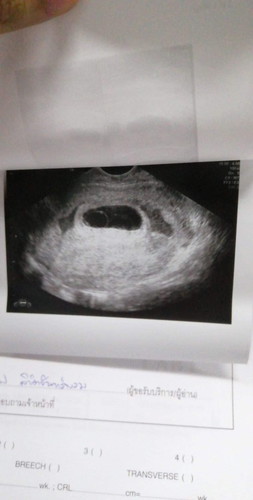

ไปซาวมา แต่หมอบอกอาจจะเป็นท้องลมค่ะ

ท้อง ได้ 2 เดือนไปซาว แต่หมอบอกมีแต่ถุง ไม่เห็นเด็ก ไม่เจอเด็ก งง.กันทั้ง 2 บ้านเลยค่ะ บ้านเรา บ้านแฟน ว่าเป็นไปได้ยังไง หมอนัดซาวอีกทีวันศุกร์ 13 รอๆค่ะ

ซาวด์ทางหน้าท้องหรือช่องคลอดคะแม่ ถ้าทางหน้าท้อง ถ้าตัวอ่อนยังเล็กมากๆ หรือเป็นคนหน้าท้องหนา อาจจะยังไม่เห็นค่ะแม่ ทางช่องคลอดจะพอมีลุ้นมากกว่าค่ะ ทั้งนี้เป็นไปได้ว่า อายุครรภ์อาจจะน้อยกว่าที่นับ เพราะไข่อาจจะตกช้ากว่ากำหนด ตัวอ่อนยังเล็กมากอยู่ จึงยังไม่พบ ก็เป็นได้ค่ะแม่ ทานโฟลิคทุกวัน พักผ่อนเยอะๆ นะคะ ซาวด์ครั้งหน้าอาจจะได้เจอกันแล้วจ้า

Đọc thêmต้องรอลุ้นค่ะ บ้านนี้ตอนแรกนับตามประจำเดือน ได้ 11 สัปดาห์ ไข่ตกช้า #พอไปซาวจิงๆได้แค่ได้แค่ 6 สัปดาห์ไม่เจอน้อง แต่พอไปอิก ตอน 9 สัปดาห์ เหนทั้งตัวและหัวใจค่ะ